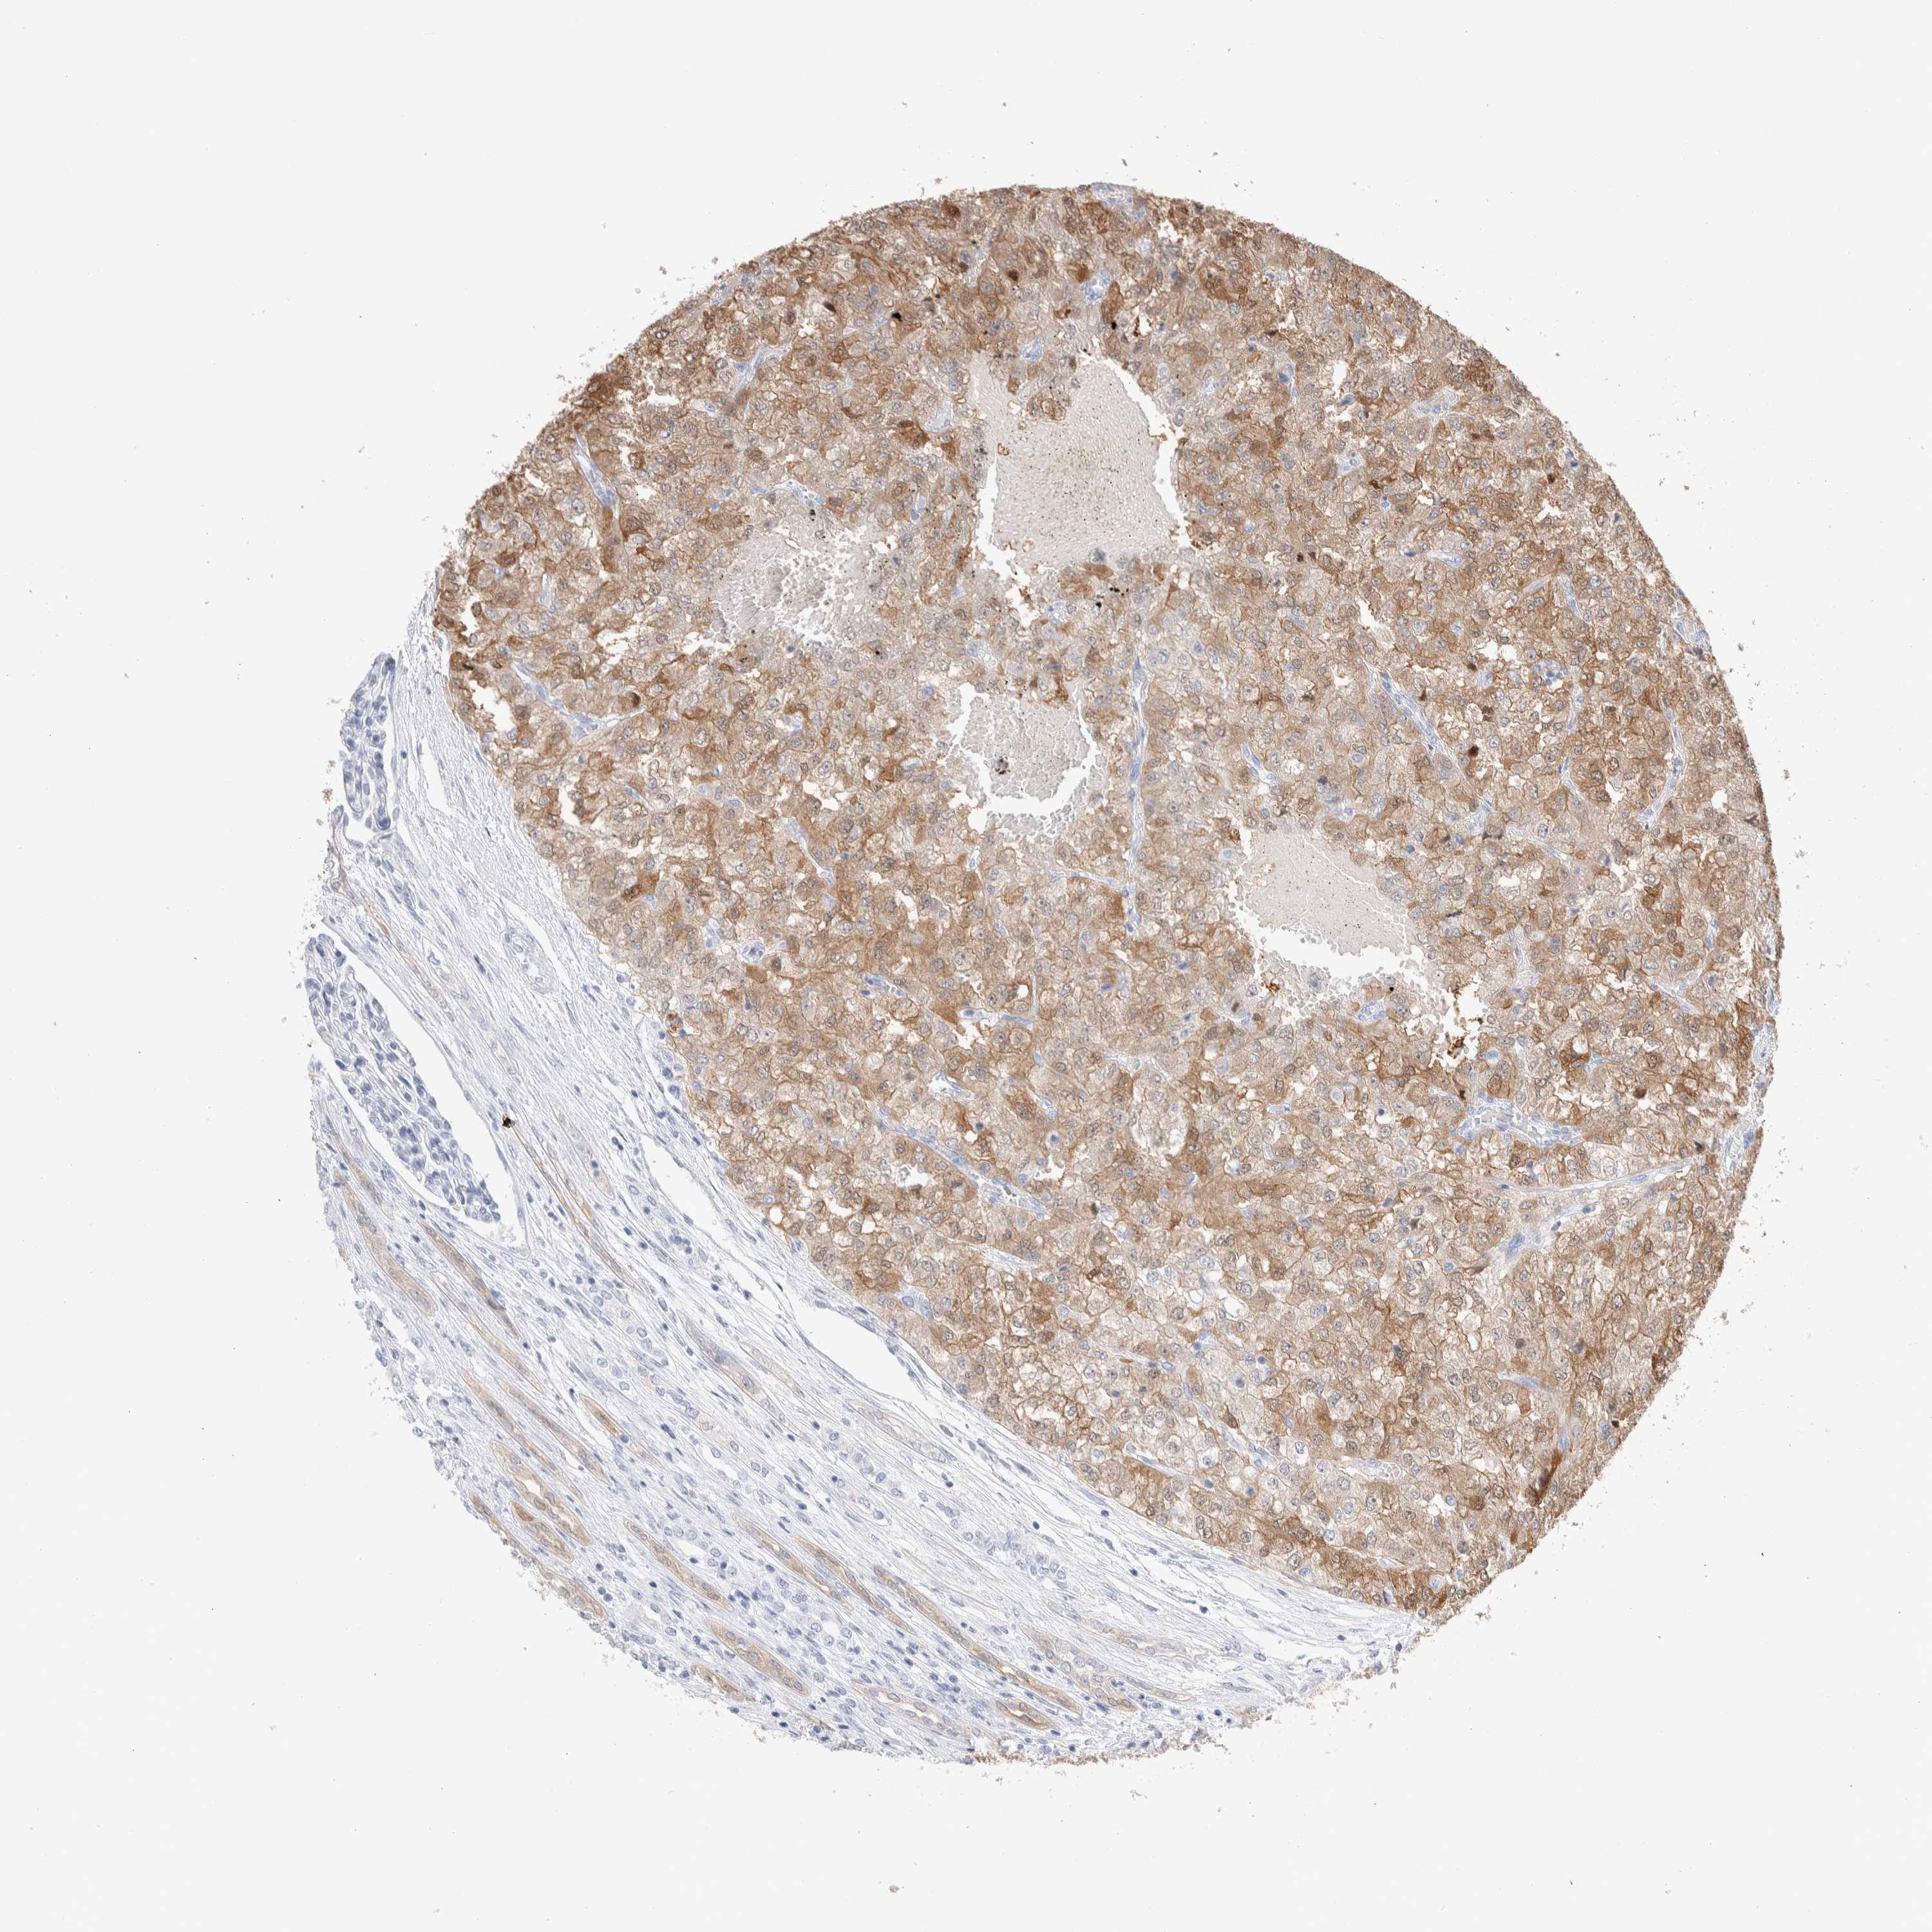

KIDNEY RENAL CLEAR CELL CARCINOMA (VALIDATION) - Interactive survival scatter ploti

The Survival Scatter plot shows the clinical status (i.e. dead or alive) for all individuals in the patient cohort, based on the same data that underlies the corresponding Kaplan-Meier plots. Patients that are alive at last time for follow-up are shown in blue and patients who have died during the study are shown in red.

The x-axis shows the expression levels (FPKM) of the investigated gene in the tumor tissue at the time of diagnosis. The y-axis shows the follow-up time after diagnosis (years). Both axes are complimented with kernel density curves demonstrating the data density over the axes. The top density plot shows the expression levels (FPKM) distribution among dead (red) and alive patients (blue). The right density plot shows the data density of the survived years of dead patients with high and low expression levels respectively, stratified using the cutoff indicated by the vertical dashed line through the Survival Scatter plot. This cutoff is automatically defined based on the FPKM cutoff that minimizes the p-score. The cutoff can be changed by dragging the vertical line or by entering a cutoff value in the square labeled "Current cut-off".

Under the Survival Scatter plot the p-score landscape (black curve; left axis) is shown together with dead median separation (red curve; right axis). Dead median separation is the difference in median mRNA expression between patients who have died with high and low expression, respectively. It is calculated as follows: median FPKM expression of dead patients with high expression - median FPKM expression of dead patients with low expression. This is intended to aid the user in visually exploring custom cutoffs and the associated p-scores and dead median separation.

Individual patient data is displayed and can be filtered by clicking on one or more of the category buttons on the top of the page. Categories describing expression level and patient information include: high, low, alive, dead, female, male and tumor stages. The scale of the x-axis can be toggled between linear and log-scale by clicking on the "x log" button. Mouse-over function shows TCGA ID, patient information and mRNA expression (FPKM) for each patient.

& Survival analysisi

Kaplan-Meier plots summarize results from analysis of correlation between mRNA expression level and patient survival. Patients were divided based on level of expression into one of the two groups "low" (under cut off) or "high" (over cut off). X-axis shows time for survival (years) and y-axis shows the probability of survival, where 1.0 corresponds to 100 percent.

GDA is not prognostic in Kidney Renal Clear Cell Carcinoma (validation)

Best expression cut offi

: 24.63

Average pTPM 21.6

Number of samples 100